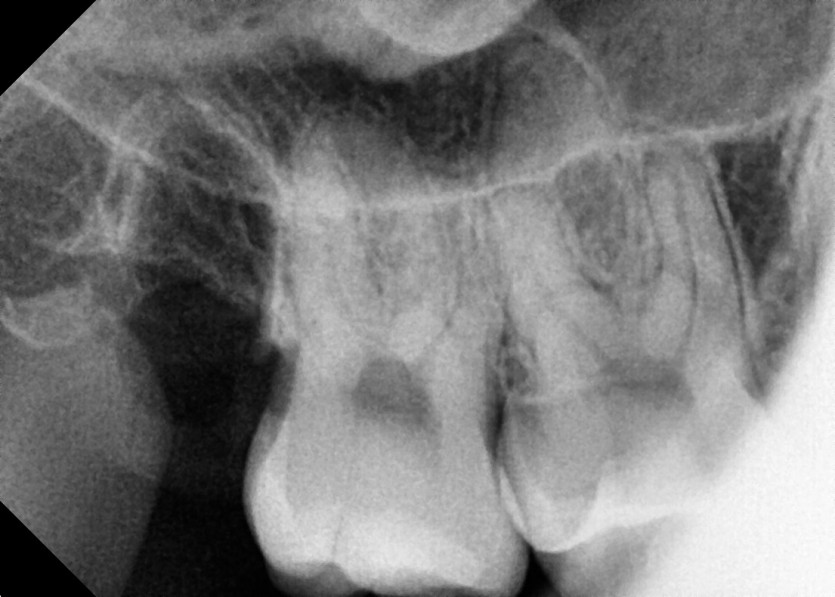

#18,48 사랑니 발치

구강 외과 전문의가 당일 발치했습니다.